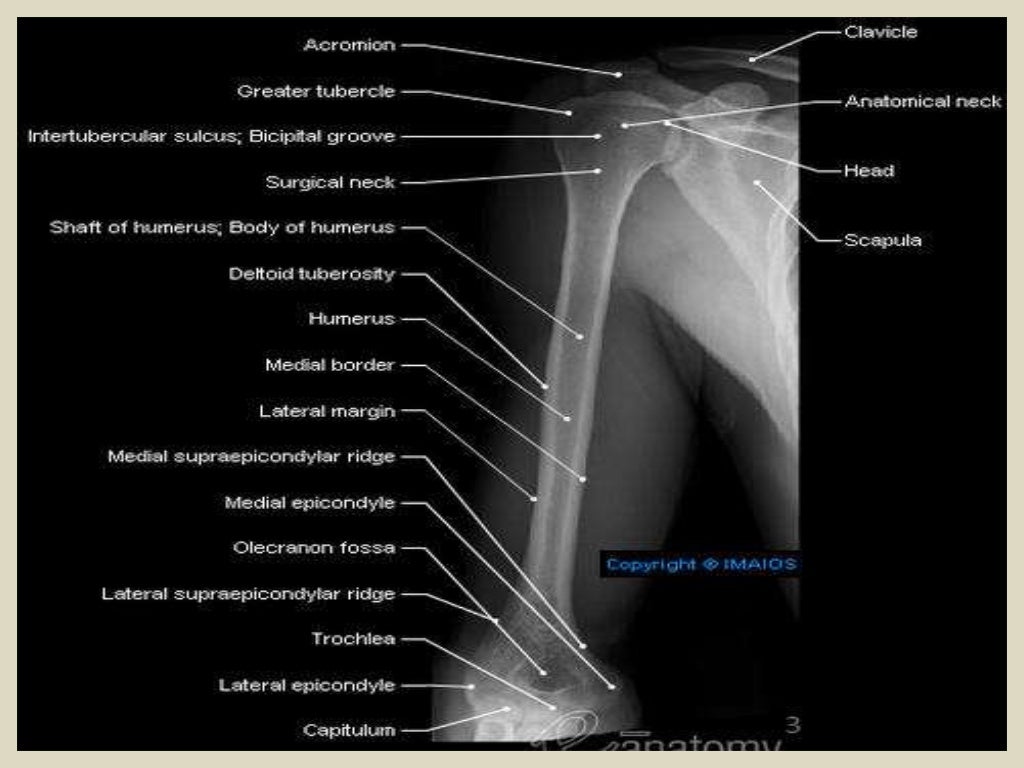

Radiographic Anatomy of the Humerus Upper Arm Anatomy Radiology imaging of the arterial and venous systems is an important component of the evaluation in many vascular disorders involving the upper extremity. It gives off the deep brachial. we created an anatomical atlas of the upper limb, an interactive tool for studying the conventional anatomy of the shoulder, arm, forearm,. long head, infraglenoid tuberosity of the scapula;. Upper Arm Anatomy Radiology.